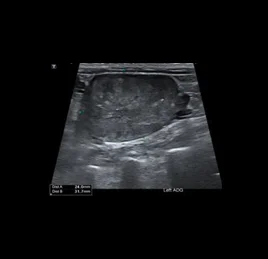

📍초음파 진단 케이스

• 방광 결석

• 부신 종양